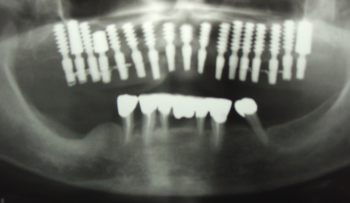

上顎にインプラント(人工歯根)を植えました。

抜いた部分の骨が回復するのを待ってから下の奥歯にもインプラントを植えました。

現在、肉でも野菜でも何でもおいしく噛めるそうです。